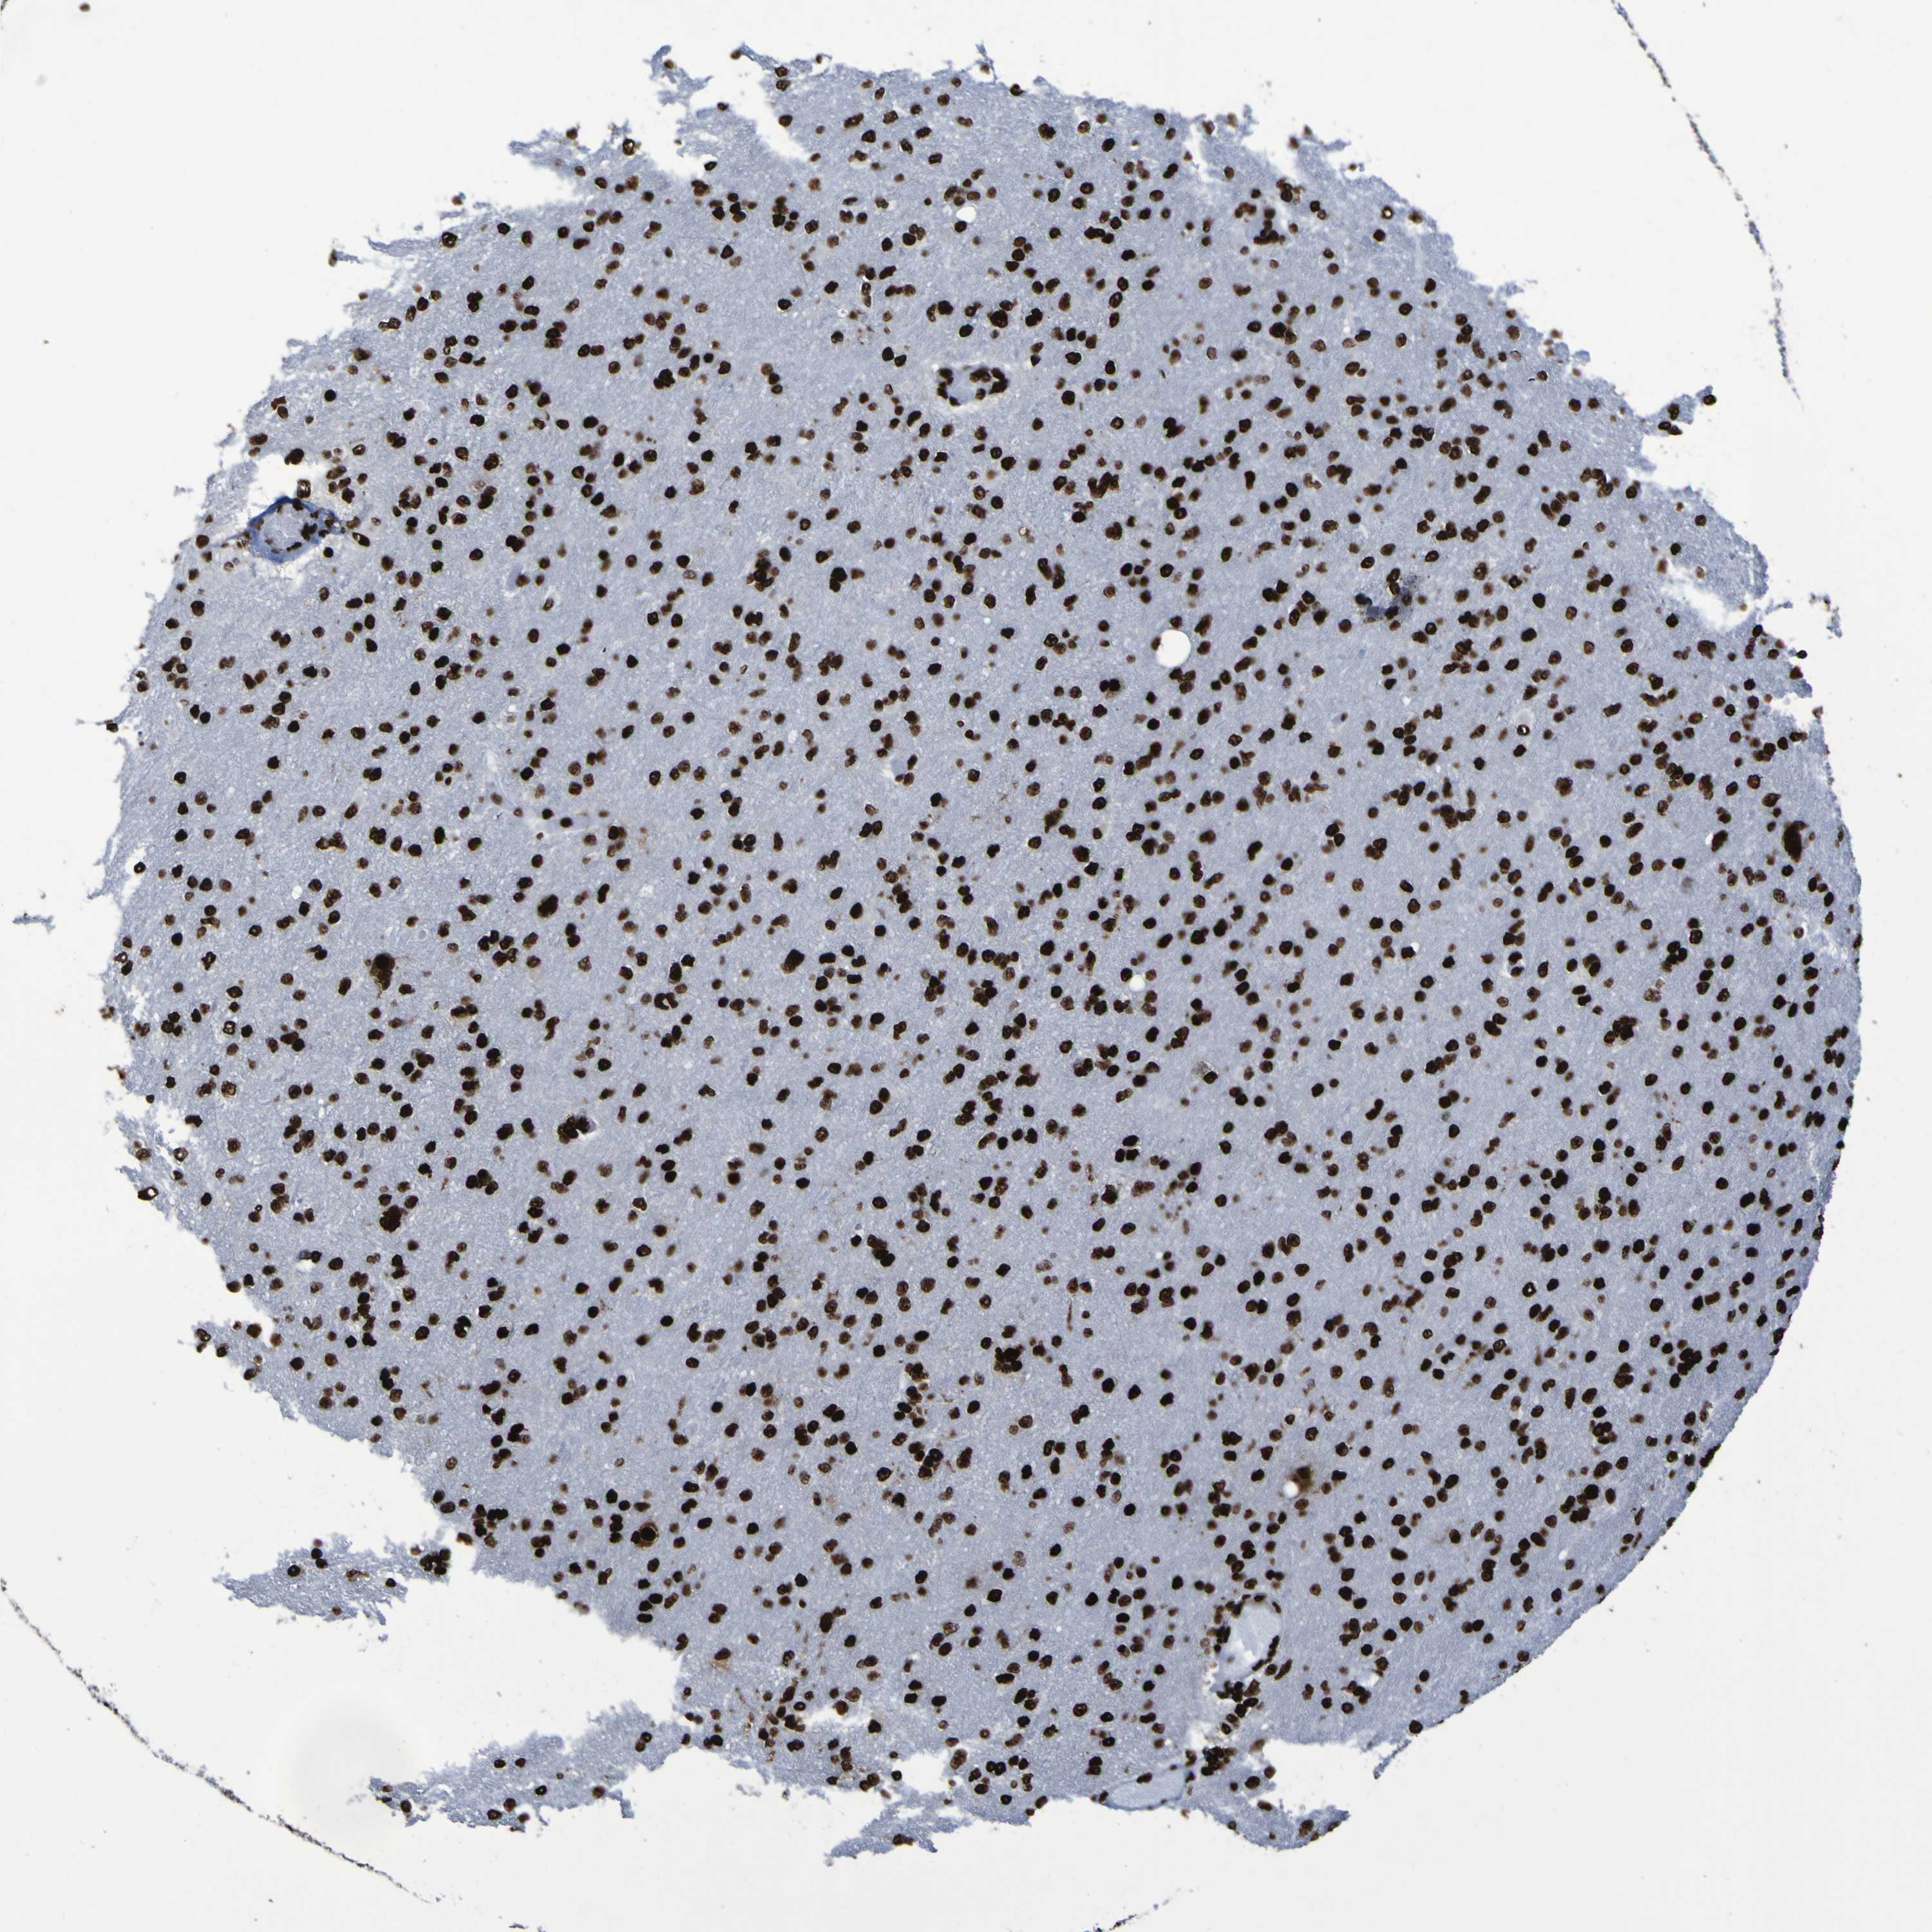

GLIOMA - Protein expressioni

A mouse-over function shows sample information and annotation data. Click on an image to view it in a full screen mode. Samples can be filtered based on level of antibody staining by selecting one or several of the following categories: high, medium, low and not detected. The assay and annotation is described here.

Note that samples used for immunohistochemistry by the Human Protein Atlas do not correspond to samples in the TCGA dataset.

Antibody stainingi

Antibody staining in the annotated cell types in the current human tissue is reported as not detected, low, medium, or high, based on conventional immunohistochemistry profiling in selected tissues. This score is based on the combination of the staining intensity and fraction of stained cells.

Each image is clickable and will lead to virtual microscopy that enables deeper exploration of all samples and also displays staining intensity scores, fraction scores and subcellular localization as well as patient and tissue information for each sample.

Antibody HPA011384

Antibody CAB012983

Staining

High

Medium

Low

Not detected

Intensity

Strong

Moderate

Weak

Negative

Quantity

>75%

75%-25%

<25%

None

Location

Nuclear

Cytoplasmic/membranous

Cytoplasmic/membranous,nuclear

Glioma, malignant, High grade

Glioma, malignant, Low grade